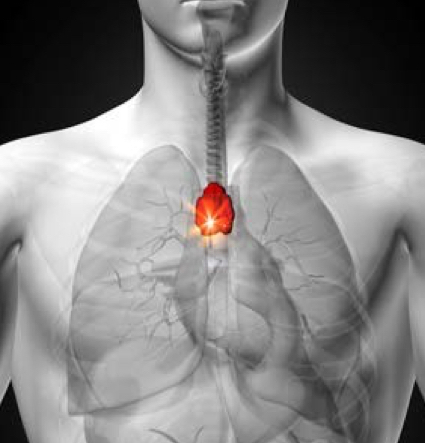

What is the function of the thymus and what happens to it over a life span?

What is the structure of the thymus?

Lobules joined by septa and encapsulated by a capsule.

Capsule and Septa made mainly by reticulun fibres in ECM

ONLY HAS EFFERENT LYMPH VESSELS